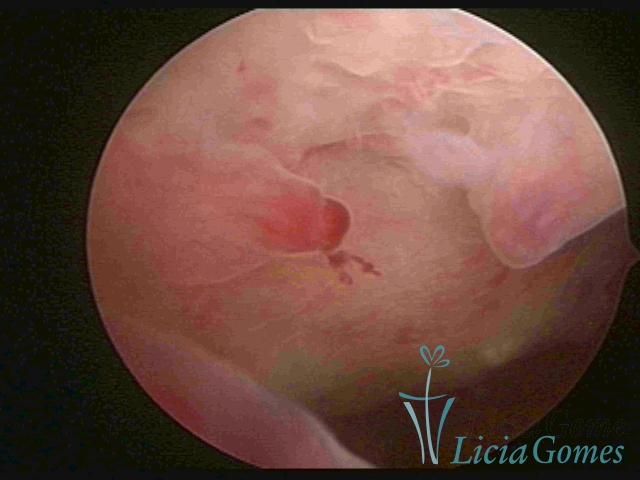

In simple hypertrophy, there is an increase in the endometrial thickness with a protuberance of the glandular punctuate, differing from the proliferative endometrial pattern by the loss of superficial reticular vascularization. Another form of simple hyperplasia is the cystic glandular hyperplasia, which also presents cystic lesions intercalated to the hypertrophic endometrium.